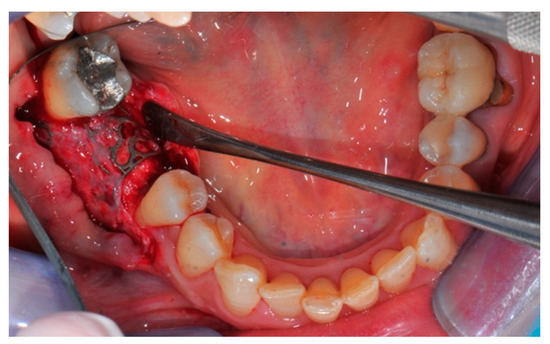

- Flap design: Soft tissue management should be as accurate as possible. The design of the flap should ensure a tension-free primary closure of the wound even after voluminous grafting of the defect. One option (preferred especially in wide vertical defects) is the execution of the so-called “poncho” flap. This technique includes a high vestibular incision of the mucosa, muscle and periosteum in order to undermine the preparation of the flap and to achieve its mobilization, followed by a deep incision in the buccal area with two additional vertical incisions that are performed at an appropriate distance from the occlusal area and the site of augmentation. After the incision, the preparation of a muco-periosteal flap and the remotion of scar tissue, a full thickness flap is raised until the bone defect is uncovered [17,18,19,20]. Finally, the positioning of the customized titanium mesh is passively tested to evaluate its fit intra-operatively (Figure 2, Figure 3, Figure 4 and Figure 5).

- Preparation of the receiving site: The exposed bone is cleaned from all of the remaining soft tissue and it is then prepared with multiple perforations using a small ball bur; this procedure is known as “bone refreshing” and it is performed to expose the cancellous portion of the residual bone, which shows a great osteo-genetic potential (Figure 6).